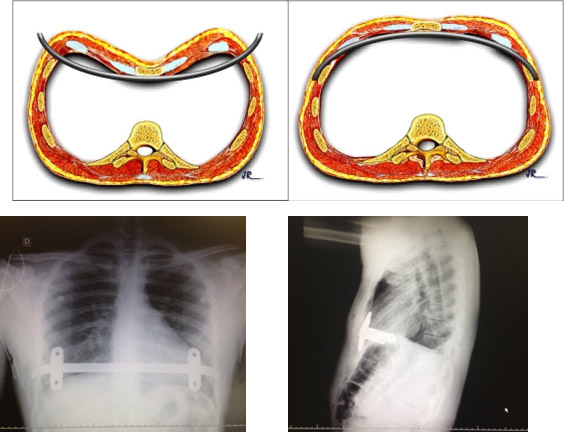

Técnica operatória minimamente invasiva: Nuss.

Através a videotoracoscopia uma barra metálica curva (moldada de acordo com a deformidade de cada paciente) é inserida da parede torácica lateral direita para a esquerda e fixada em posição retro esternal no ponto de maior deformidade. Após sua introdução, sofre uma rotação de 180º para que a curvatura da barra e a da parede torácica anterior seja coincidente.

Estabilizadores metálicos subcutâneos nas extremidades da barra a mantêm em posição correta até sua retirada, que em geral se da após 36 meses (3anos).

Rx Tórax no 1º Pós-operatório com a barra

Pré-opertório: cirurgia de Nuss

14º Pós-operatório: cirurgia de Nuss